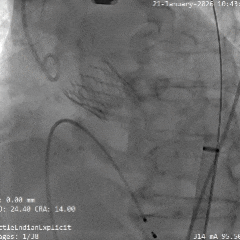

术中影像

根部造影

瓣叶活动差,可见明显反流,猪尾导管测量跨瓣压差约50mmHg

20mm球囊预扩

微腰微漏,左右冠均显影

造影确认瓣环与瓣膜位置

瓣膜0位初始定位释放,展开过程微微下移

全展开位造影评估

瓣膜呈直筒型,微腰,大弯侧约瓣下3mm,少量反流,冠脉显影

瓣膜无张力脱钩

植入后造影评估

瓣膜位置合适,可见少量反流

多角度造影评估

瓣膜形态可,冠脉显影,猪尾测量压差为0